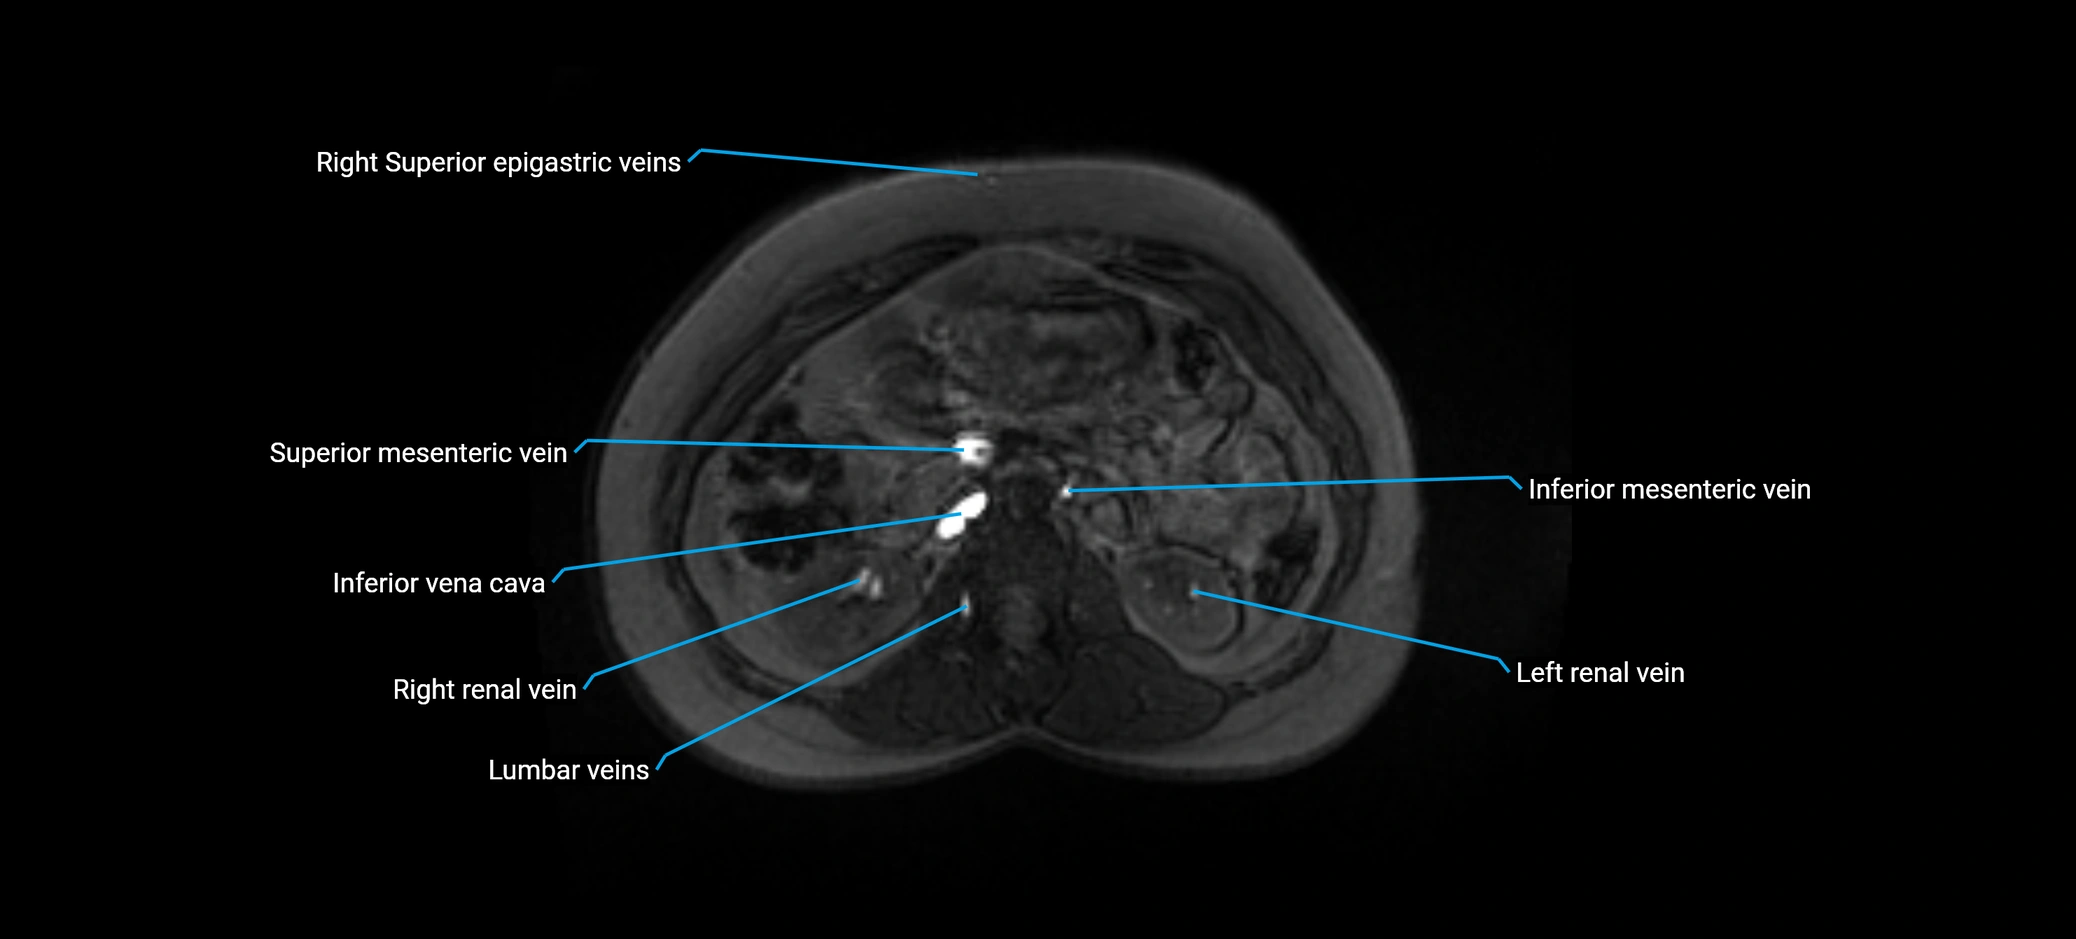

MRI image

image